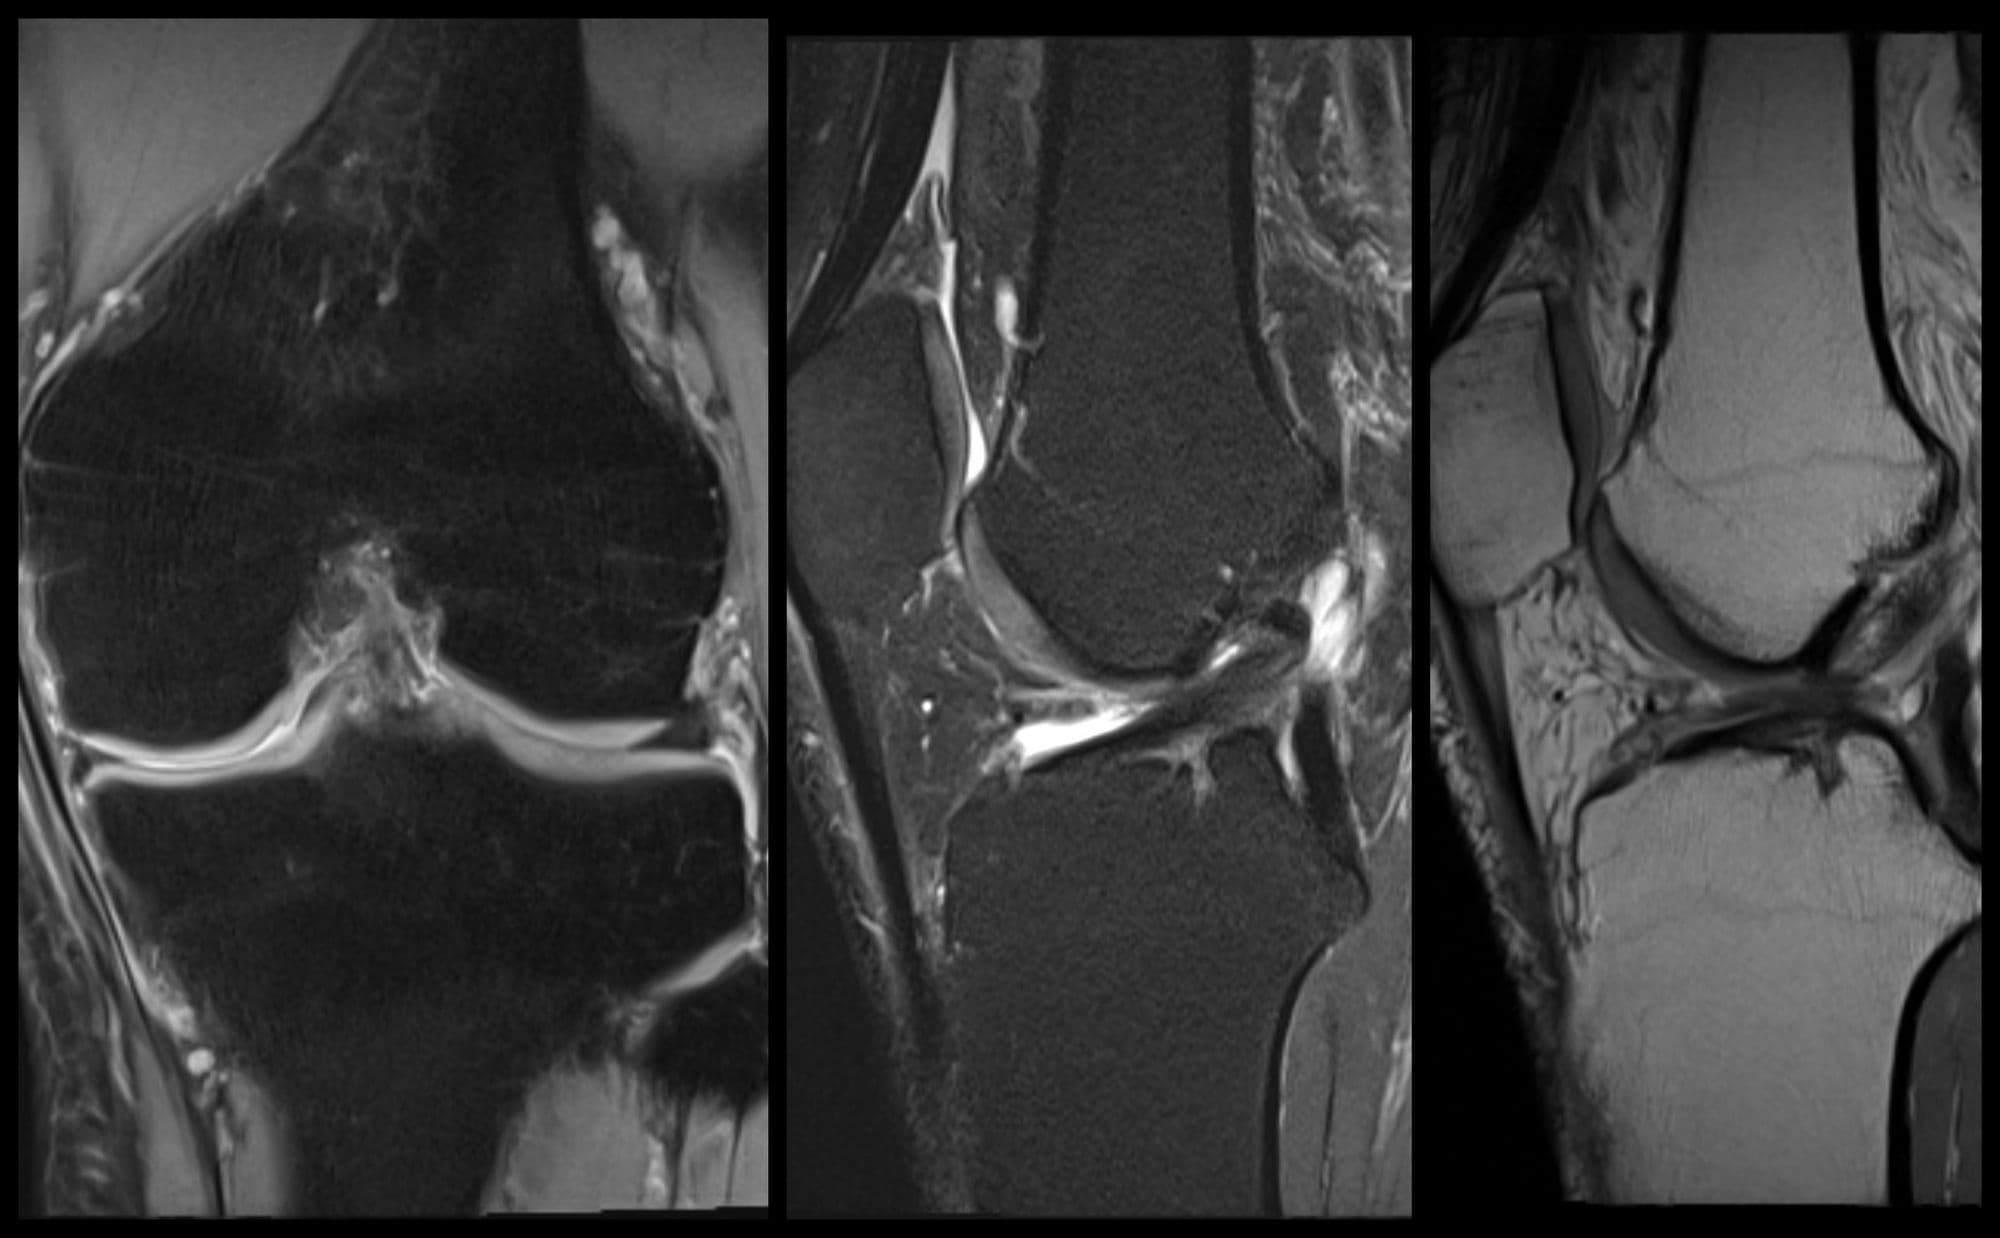

Imaging